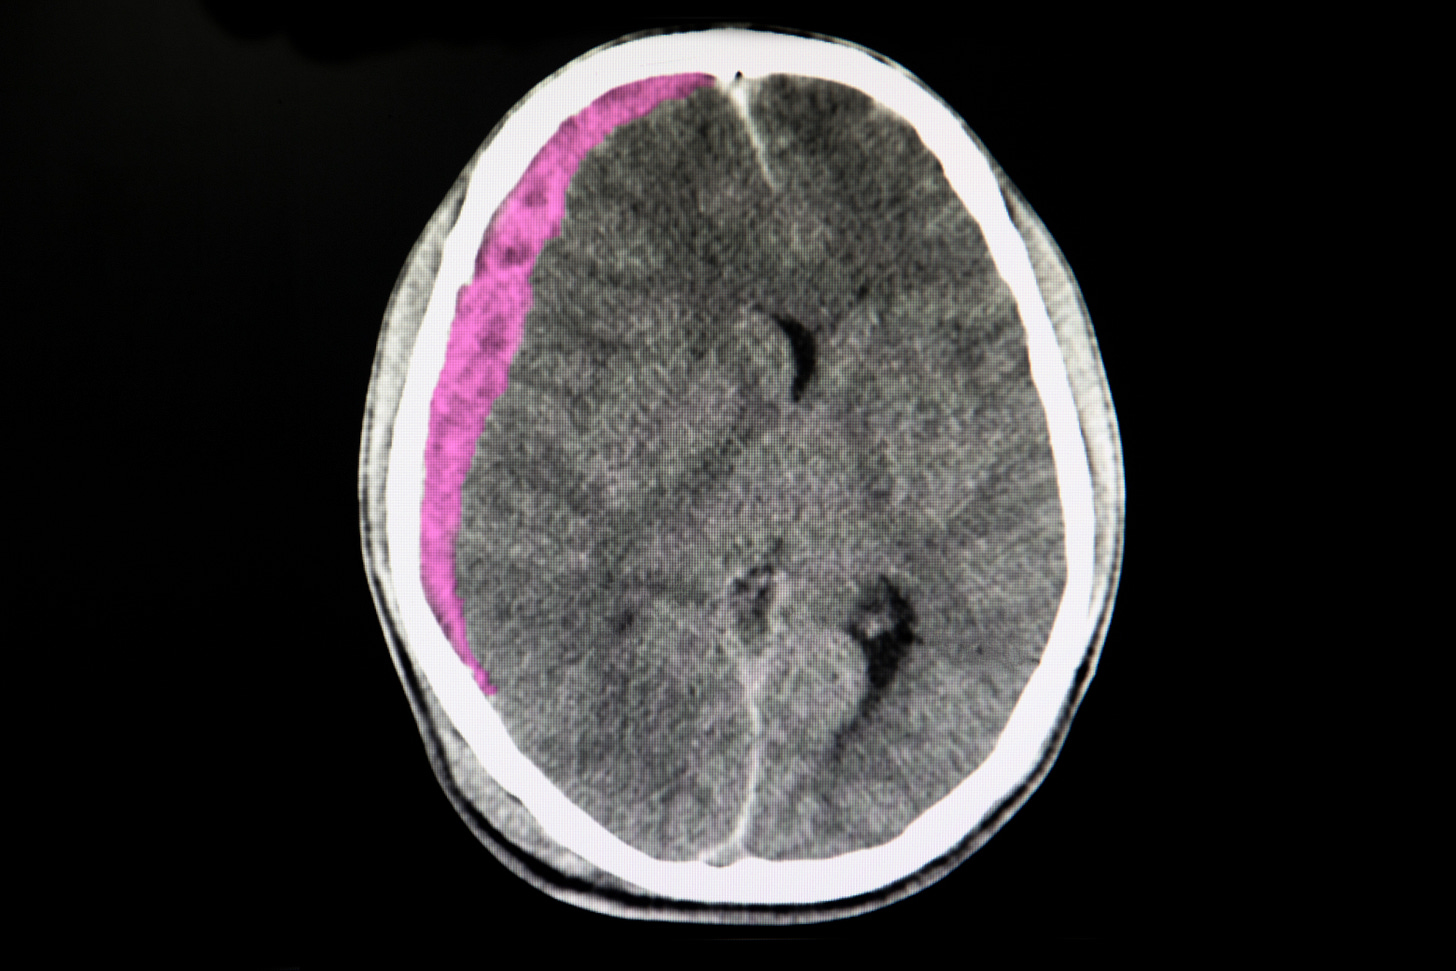

MMA embolization instead of surgery in subacute or chronic subdural hematoma (MAGIC-MT trial)*

*in China

After surgeons had made the decision whether or not to operate on 772 patients with subacute or chronic subdural hematoma, subjects were then randomized to receive middle meningeal artery (MMA) embolization with Medtronic’s Onyx™ product, or usual care. Everyone involved was unblinded and bias was inevitably introduced at the time of the surgeon’s decision. That being said, there was no significant reduction in the recurrence or progression of subdural hematoma within 90 days (6.7% in the embolization group vs 9.9% in the usual-care group), but fewer serious adverse events occurred in the embolization group (6.7% vs. 11.6%, P=0.02).